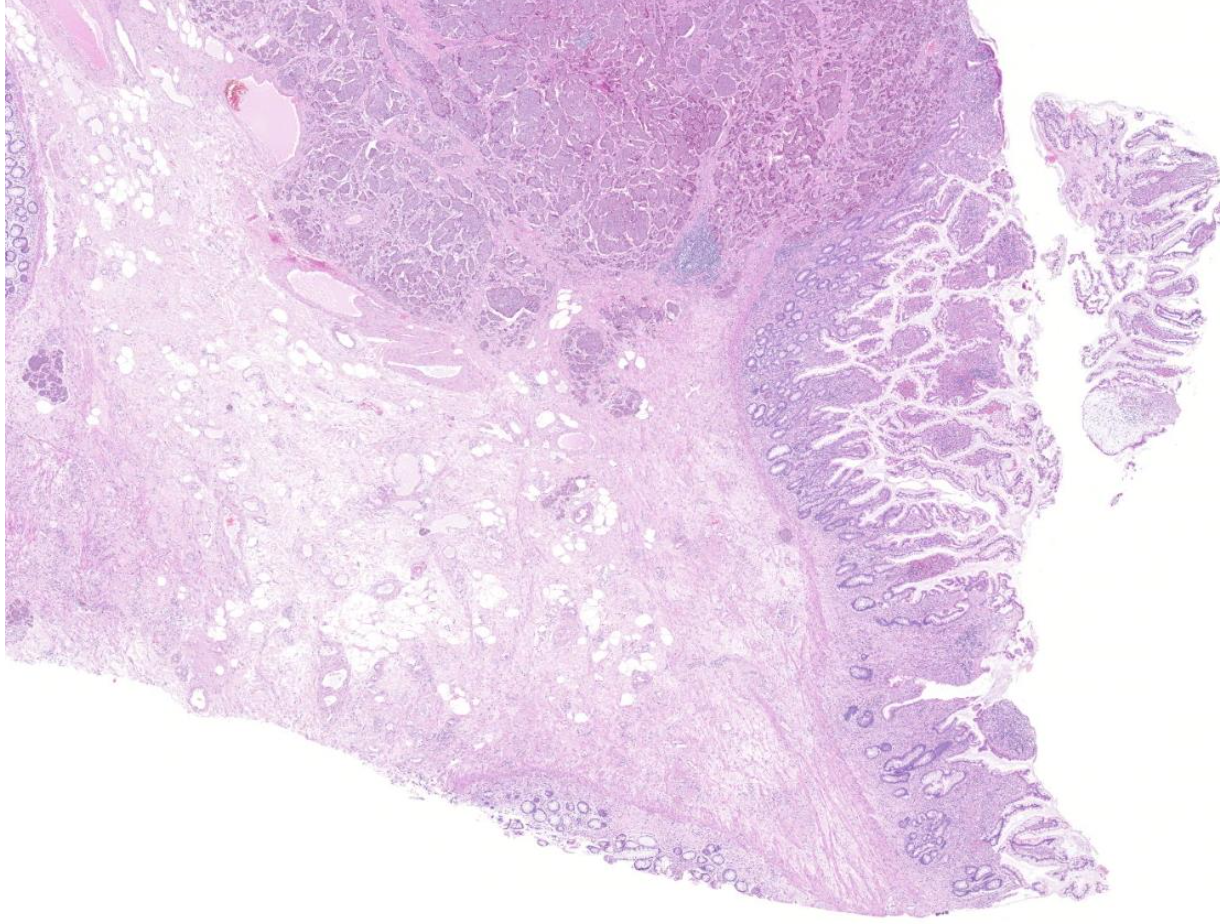

Diagnose?

Adenokarzinom des gastroösophagealen Übergangs = Barettkarzinom

Viel häufiger als Plattenepithel-CA, wird immer irregulärer je höhergradig und tieferreichender der Tumor ist, Dysplasie ist Vorstufe und Notwendigkeit zur Therapie